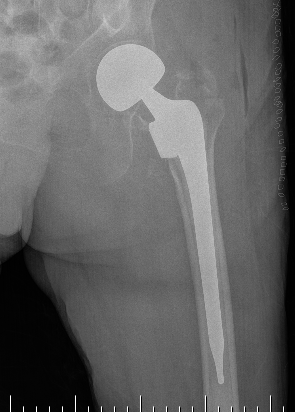

Hemiarthroplasty / Total hip replacement

Indications

- severe comminution

- salvage of failure of previous fixation

Technical

- may need calcar replacement

- may need greater trochanter fixation